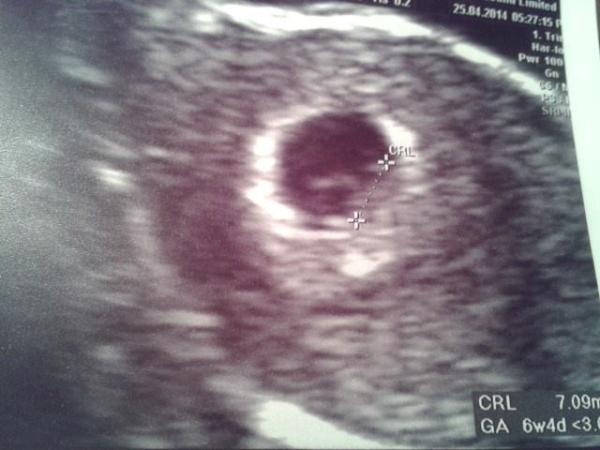

And Emily, do you mean sharing scans? If so, it's possible to add pictures to posts, I'm going to attempt to put my 6+4 scan on (but on the kindle, it could go wrong!)